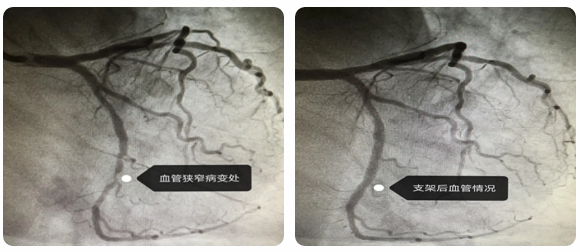

手术前后血管对比

针对患者身体情况,科主任索云锡与医师团队为他制定了合理的治疗方案,三天后,进行经皮冠状动脉介入治疗(PCI),开通冠状动脉前降支、回旋支血管,解决了冠状动脉狭窄问题,成功预防了心肌梗死等危重症的发生。

由于患者病情复杂,心内二科团队连夜完善综合治疗方案,平稳降压、综合治疗。当患者各项指标平稳后,为患者实施经皮冠状动脉介入治疗(PCI),植入支架,改善冠状动脉狭窄情况,恢复正常血流灌注,为患者的早日康复提供了有力保障。